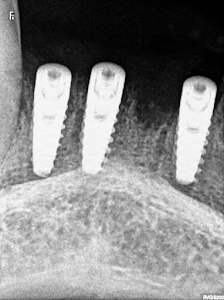

Welcome to our gallery

See how our company transforms ideas into reality. This gallery is a visual testament to our work and achievements.